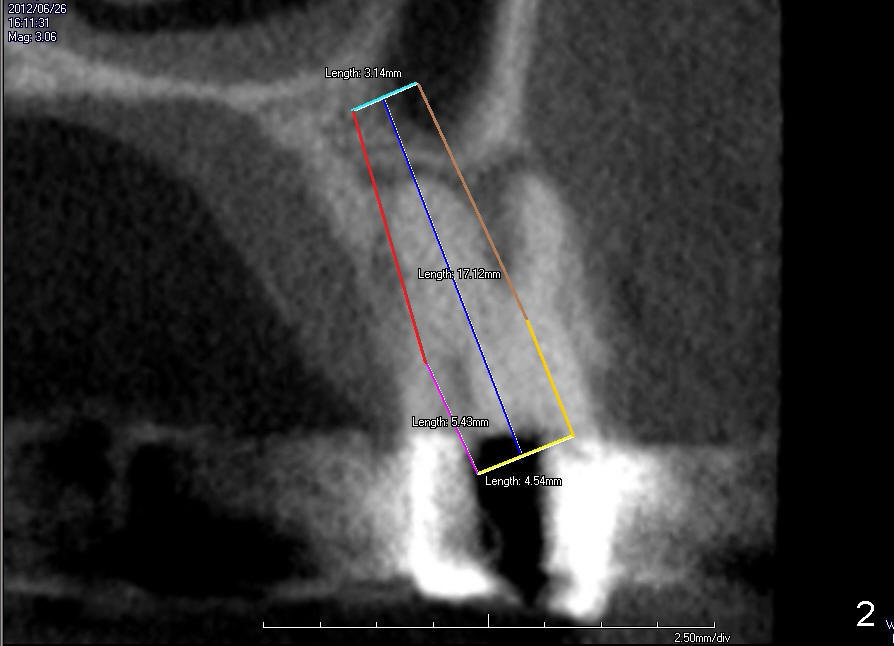

The tooth #13 has broken down to residual root now. CBCT sagittal (Fig.1,3) and coronal (Fig.2,4) sections show designs of T (4.5x17 mm Fig.1,2) and D2 (Fig.3,4) implants. Which is better? It appears that sinus lift with bone graft is expected.

In fact, D2 implant is placed.